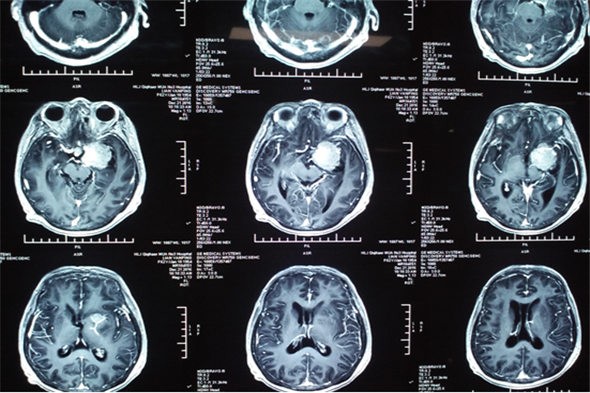

廉女士现年62岁,既往有垂体瘤病史1年左右,随着肿瘤的不断长大,出现精神症状,有言语迟钝及行动受限等表现。患者曾因此病周转于周边各大医院,后了解到我院成功治疗多例此类疾病,治疗效果良好,遂慕名来到我院治疗。由吴卫东主任及科室成员共同诊治,进行头部核磁,显示蝶鞍、蝶窦及左侧鞍旁占位性病变,增强见肿瘤强化明显,直径大于5.0cm,诊断为侵袭性垂体瘤。吴卫东主任带领科室成员共同讨论商议,制定出详细的治疗方案,并做好术前准备,开启了又一次充满挑战的手术治疗。

当日,先由麻醉医生为患者麻醉,在手术室护士的密切配合下,由吴卫东主任为患者施行手术,术中吴卫东主任凭借精湛的手术技能,在开颅切除蝶骨脊旁5.0cm肿瘤后,在狭小的动脉与各个神经缝隙间精细操作,以刮匙完全刮除鞍内肿瘤,保留周边血管及神经,手术进行的十分成功,在术后的第一天患者就意识清醒,无功能缺失。

垂体瘤在临床出现症状较多,主要是肢端肥大,巨人症及库欣氏综合征,亦可出现泌乳或性功能低下等症状,垂体瘤从形态上可分为:微腺瘤、大腺瘤、巨大腺瘤。超过3cm即为巨大腺瘤,该患者肿瘤直径为5cm,为巨大腺瘤。其周围为颈内动脉,视神经及动眼神经等重要组织结构,手术风险较大,神经外二科成立以来垂体瘤切除术已是常规手术,但此巨大垂体瘤实属罕见。吴卫东主任精准的判断及娴熟的手术技巧,神经外二科团队及麻醉科快速、高效的配合再一次创造了奇迹。

术前头部MRI